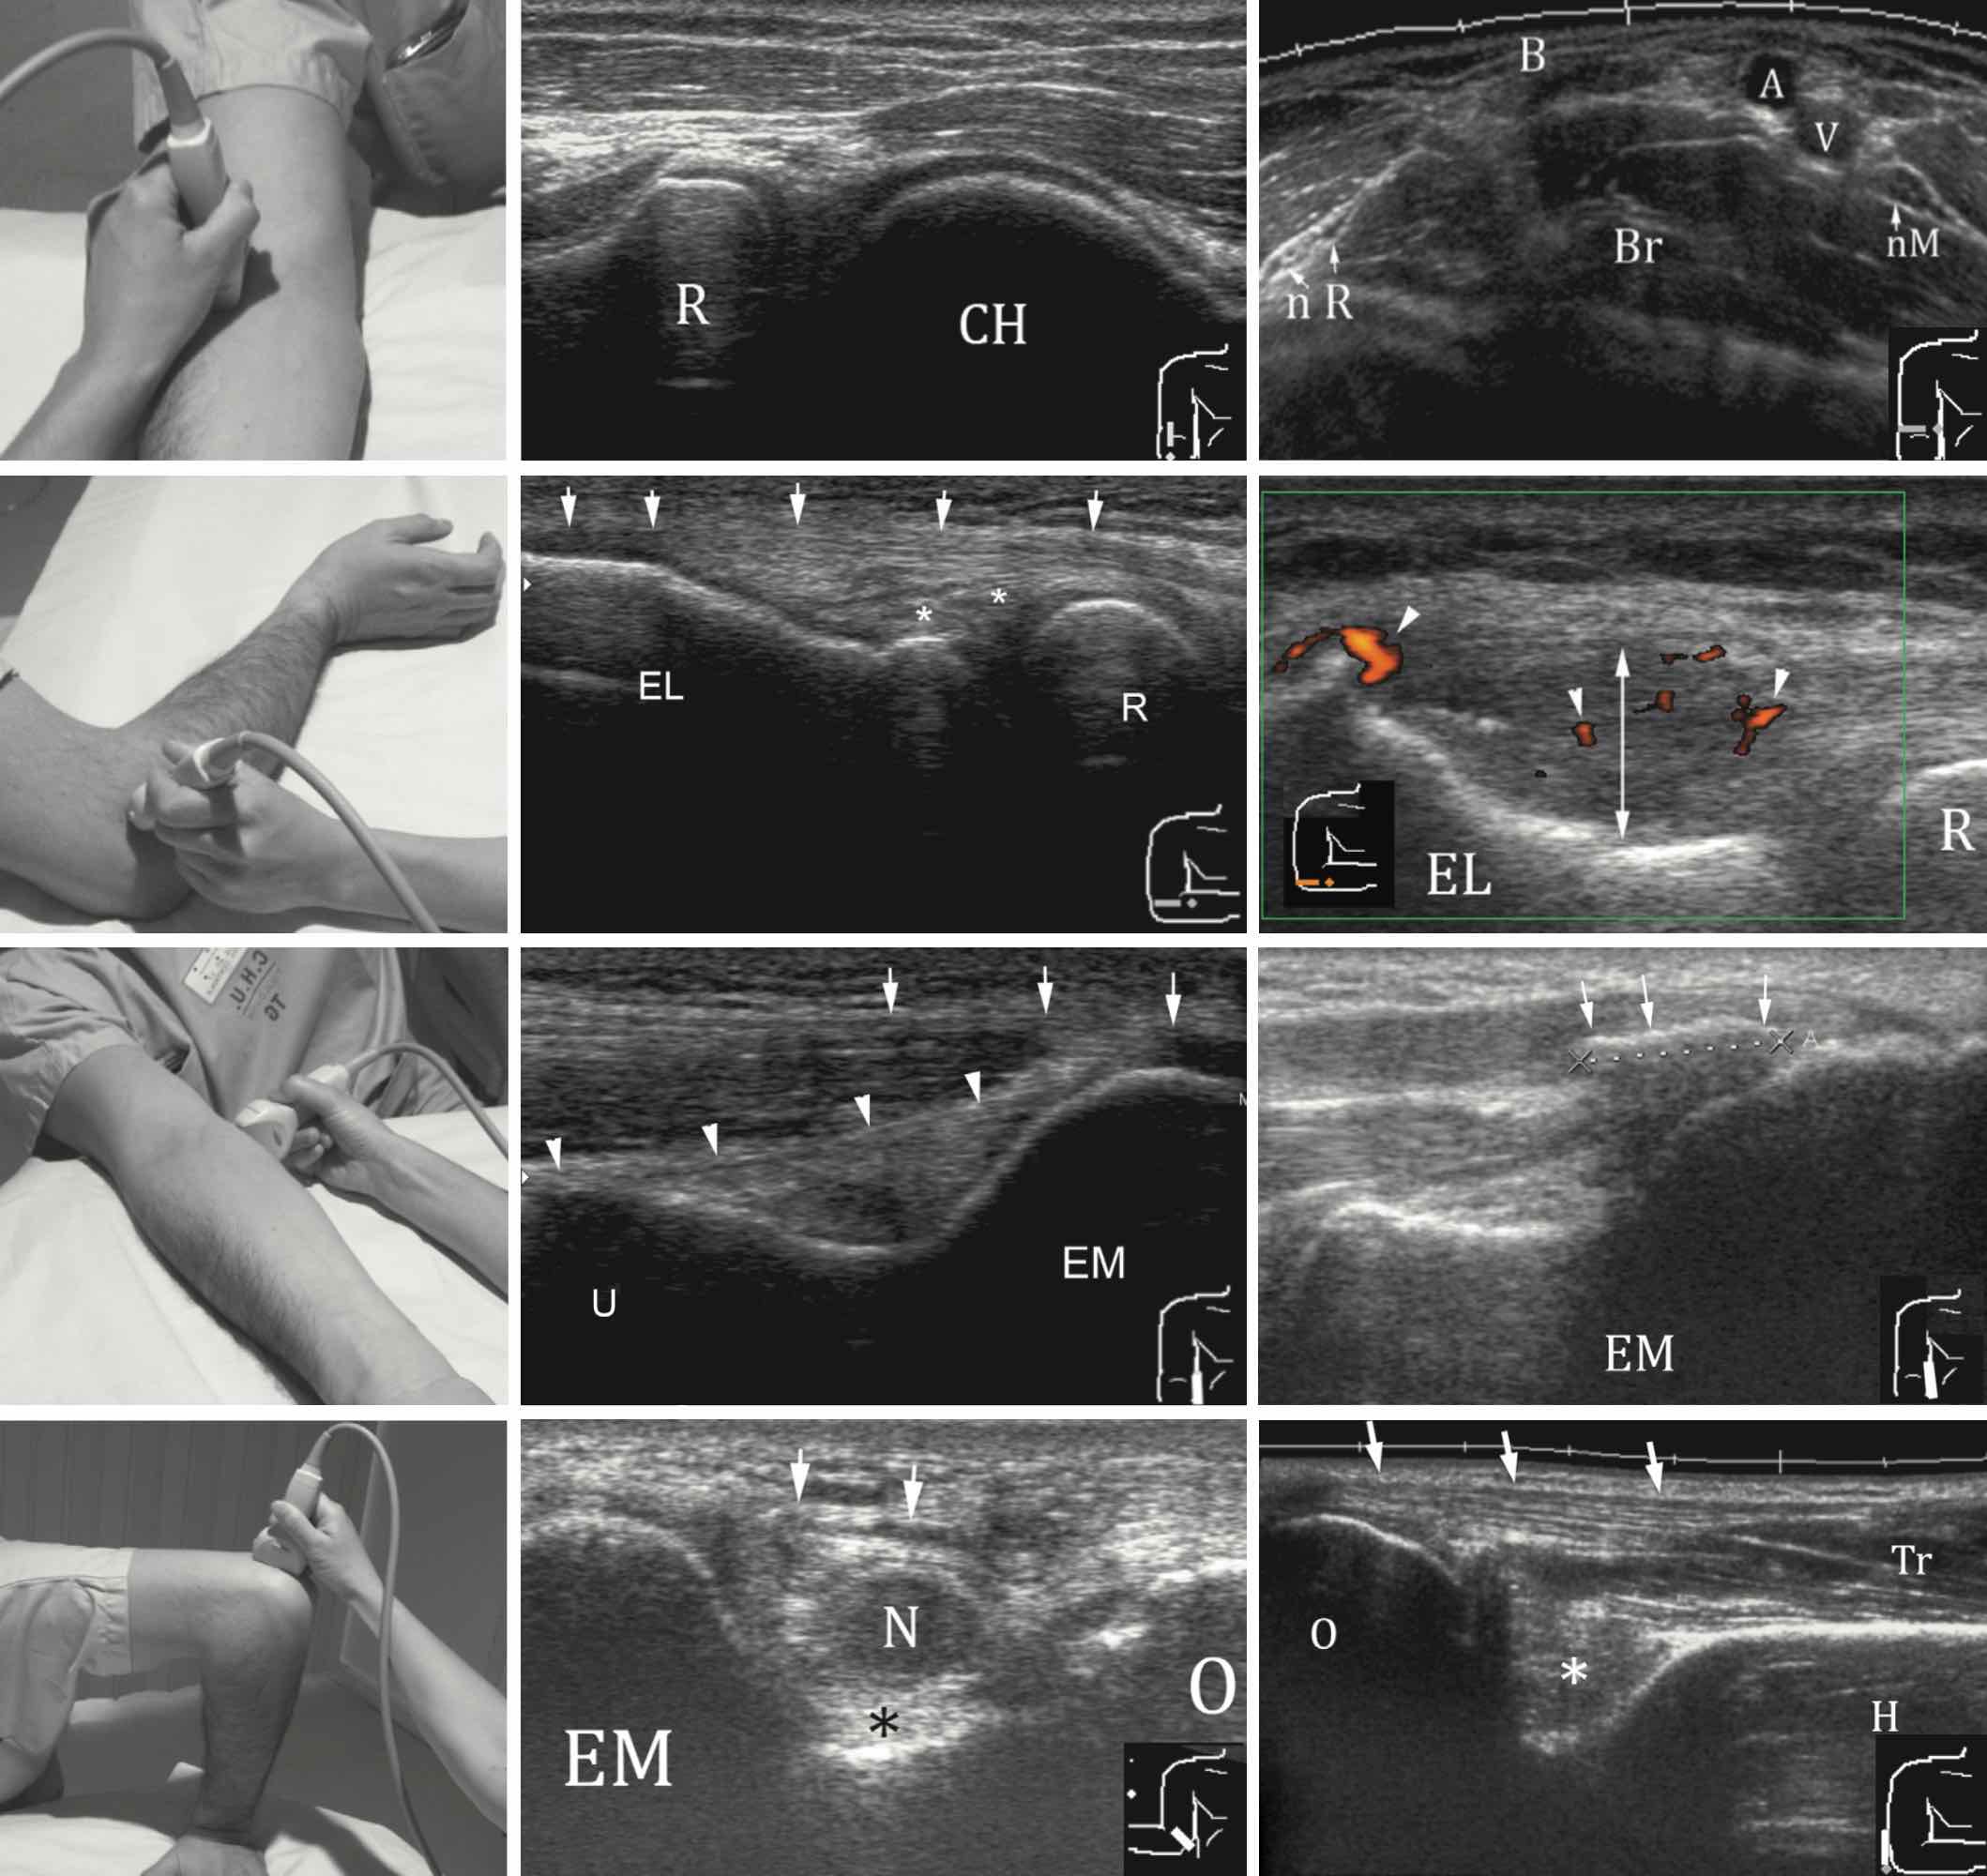

Epicondylite

Pas d'épanchement articulaire.

Intégrité des tendons communs des épicondyliens latéraux et médiaux.

Pas d'anomalie des tendons distaux des muscles biceps et triceps.

Aspect normal du nerf ulnaire dans son tunnel.

Nerf ulnaire

Nerf ulnaire en place au sein de la gouttière épitrochléo-olécrânienne.

Aspect fasciculaire sans disparité de calibre ni augmentation de sa surface de section.

Absence de luxation lors des manœuvres dynamiques.

Pas de lésion compressive extrinsèque.

Hygroma

Collection anéchogène compressible sous-cutanée rétro-olécrânienne mesurant mm.

En son sein flottent des lobules graisseux hyperéchogènes, sans lésion suspecte.

Infiltration et discrète hyperhémie des tissus mous adjacents.

Pas d'épanchement articulaire huméro-radial ni huméro-ulnaire.